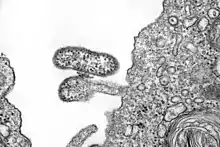

| electron microscope image of Chapare virus | |